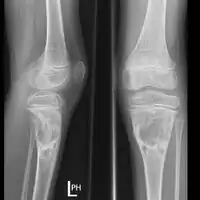

X-ray: ABC large long bone of lower leg near knee

X-ray and CT scan show lytic expansion lesions with clear borders.[1] Expansion of cortex gives the lesion a balloon-like appearance. Larger lesions may appear septated.[10] MRI reveals fluid levels.[1] Bone scan shows outer radiotracer uptake, with a central dark area.[1]